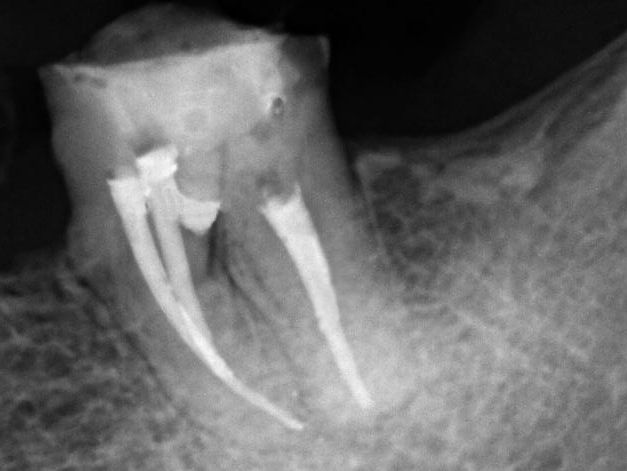

Paciente do gênero feminino, 47 anos, apresentou-se com quadro clínico de extensa perfuração iatrogênica da região de furca do elemento dental 36 (figuras 1 e 2), associado à perda óssea radiograficamente, fístula vestibular e dor à palpação.

Na sequência, a perfuração foi tratada com a limpeza e a regularização da mesma, empregando inserto ultrassônico diamantado (E7D/Helse/Brasil). Como complemento ao processo de descontaminação intracanal e da região de furca, foi realizado uma troca quinzenal de Hidróxido de Cálcio (Ultracal/Ultradent/USA), observando a remissão de toda a sintomatologia.

A obturação foi realizada pela técnica termomecânica Híbrida de Tagger (figura 3), por meio do emprego de GutaCondensor (Maillefer/Suiça), cones de guta-percha TP (Dentsply/Brasil) e cimento obturador à base de M.T.A. Fillapex (Angelus/Brasil).